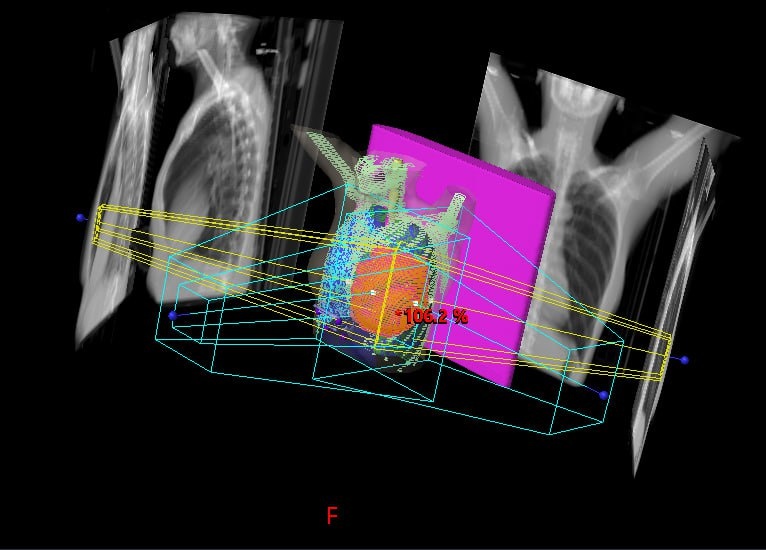

Курс длится около 3 недель (сеансы по 10-15 минут, 5 дней в неделю). Это похоже на рентген, только мощнее и точнее. Современные аппараты бьют прицельно по опухолевой зоне, максимально щадя сердце и легкие. 🎯